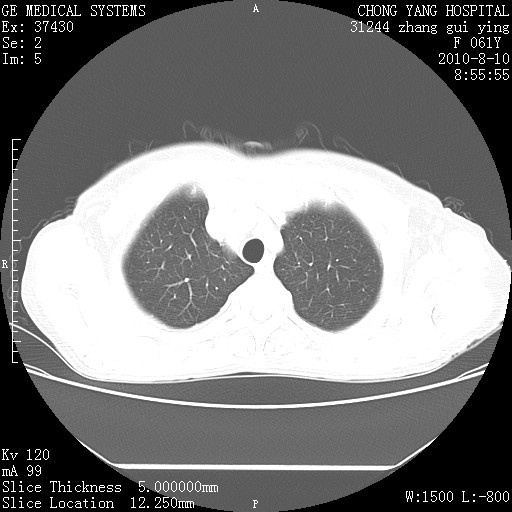

标题: CT28314:F61Y胸部增强,发热咳嗽一周入院,后面的为一周前平 [打印本页]

标题: CT28314:F61Y胸部增强,发热咳嗽一周入院,后面的为一周前平

右肺下叶中心性肺癌可能性大

1、支持考虑右侧中央型肺癌伴右肺中叶节段性不张及下叶支气管黏液痰栓    2、左肺上叶舌段感染。

支持右下肺中央型肺癌并左上肺感染.

我也觉得右肺中叶支气管受累

支持3楼意见,还要考虑:纵隔及肺门淋巴结转移、右侧少量胸腔积液。

支持考虑右侧中央型肺癌

确切的说:1:右肺下叶中心型肺癌侵及中叶支气管并中叶不张,纵膈淋巴结转移。2:左肺舌叶炎症。3:右侧胸腔少量积液

块影平扫32hu,动静脉期62-70hu.